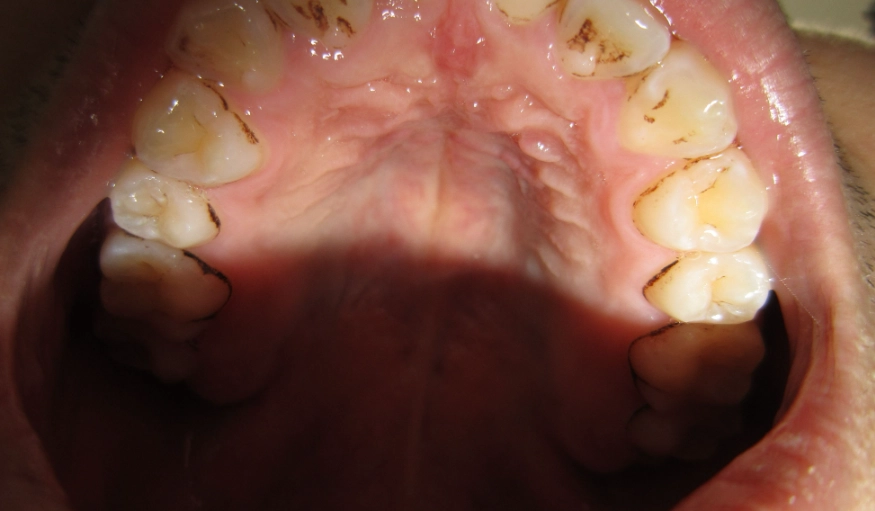

第一步:先對號入座!7種常見腫脹原因圖文對照

原因沒搞清楚,所有處理都是白費力氣。牙齒後方腫脹,九成離不開下面這七種狀況。你可以先對著鏡子,看看自己的情況比較像哪一種。

| 1. 智齒冠周炎 | 腫脹集中在最後一顆牙(智齒)的牙齦瓣上,可能覆蓋部分牙冠。按壓有膿或血水滲出,伴隨劇烈抽痛、張口困難。 | 20-35歲年輕族群最常見。飯後食物殘渣卡進智齒與牙齦的縫隙,清潔不到而引發感染。 | 高(易惡化) |

| 2. 牙齦膿瘍 | 牙齦上鼓起一個圓形、界限分明的小腫包,像「青春痘」。可能反覆出現,擠壓後有惡臭膿液,但膿排出後腫痛會暫時緩解。 | 蛀牙很深、牙齒有裂縫、或之前根管治療不徹底,導致牙根尖發炎,膿液從牙齦找出口排出。 | 中高(需根管治療) |

| 3. 牙周膿瘍 | 腫脹範圍較大,可能沿著牙齦緣蔓延。牙齒有明顯晃動感,牙齦與牙齒間有深口袋,按壓牙齦會流膿。 | 長期牙周病患,因清潔不當導致牙周囊袋深處細菌大量滋生,急性發作。 | 高(恐傷骨頭) |